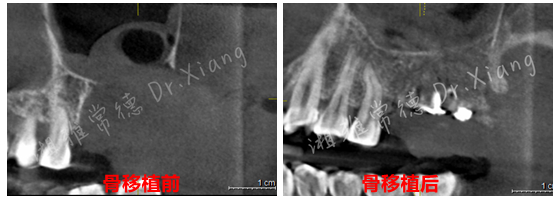

误拔出的牙及颌骨

2024年末,该患者因外院不正规的拔牙造成左上颌大面积骨缺损。为寻求颌骨修复,在常德多家医疗机构就诊,均告知难度大建议前往长沙。患者不想奔波,经朋友介绍后来到湘雅常德医院就诊。口腔科主任伍栋接诊了患者并为患者制定了详细的治疗计划。伍栋主任指出:患者因拔牙造成颌骨大面积缺损,目前需要分二步处理。第一,先行颌骨缺损的骨移植;第二,待骨移植成功后,再行缺牙的种植修复。经过周密的术前规划和准备,口腔颌面外科团队在全身麻醉下为患者成功施行了“游离髂骨移植修复术+牙槽植骨成形术”。手术团队巧妙地以患者自身的髂骨作为移植材料,采用数字化3D设计与打印技术,在术中精准截取髂骨并完成上颌骨缺损的定制化重建,成功恢复颌骨及牙槽嵴的生理性高度与宽度,实现解剖结构的精准复原,并应用了微型钛板钛钉内固定系统来确保移植骨的稳定愈合。

经过9个月骨愈合后,患者复查锥形束CT,骨愈合十分满意。9月中旬,向峰医师种植团队成功为患者实施了第二步的手术,取出内固定装置的同时为患者成功微创的植入2枚种植体,完成了患者左上颌区域的软硬组织的自然恢复和改建。